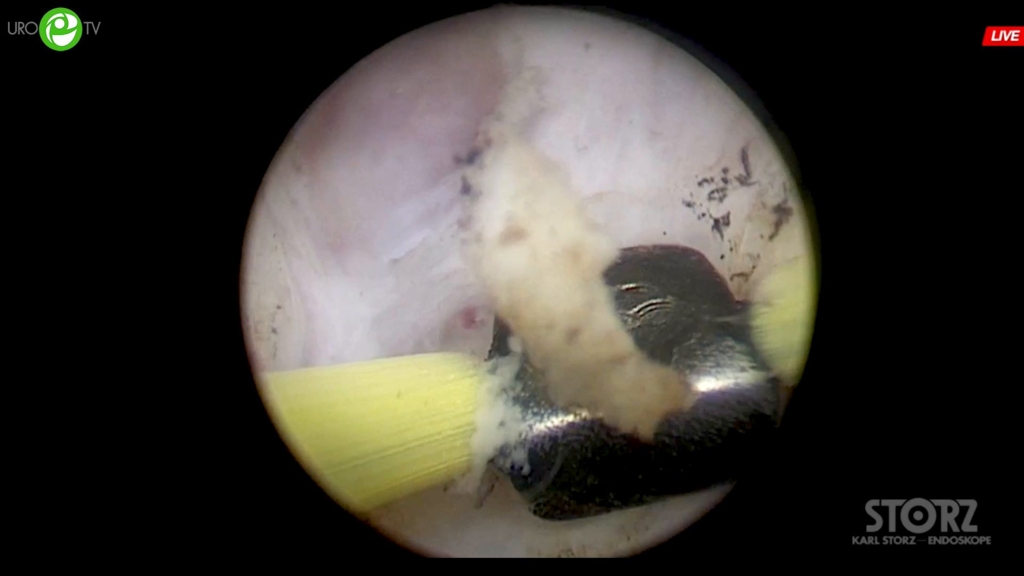

Сорокин Н.И. - Биполярная энуклеация простаты

07 мая 2020

ДГПЖ